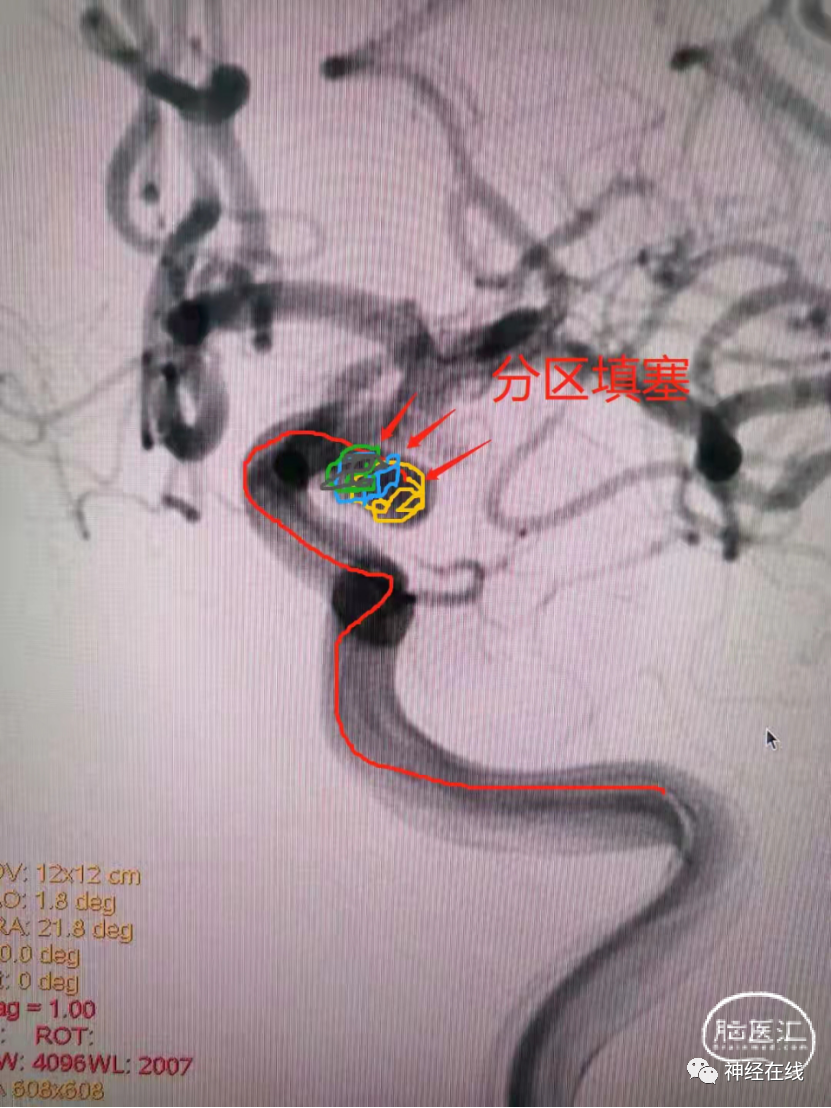

③分部填塞技术:将小规则宽颈动脉瘤以及腊肠样动脉瘤设想成2~3个形态规则的部分,尤其要将瘤颈与部分瘤体作为一个整体,分部逐一填塞。但技术前提是实际操作时必须能将微导管安全超选至预选部位,同时,填塞弹簧圈时微导管必须保持稳定。

长条状破裂后交通动脉瘤弹簧圈栓塞病例